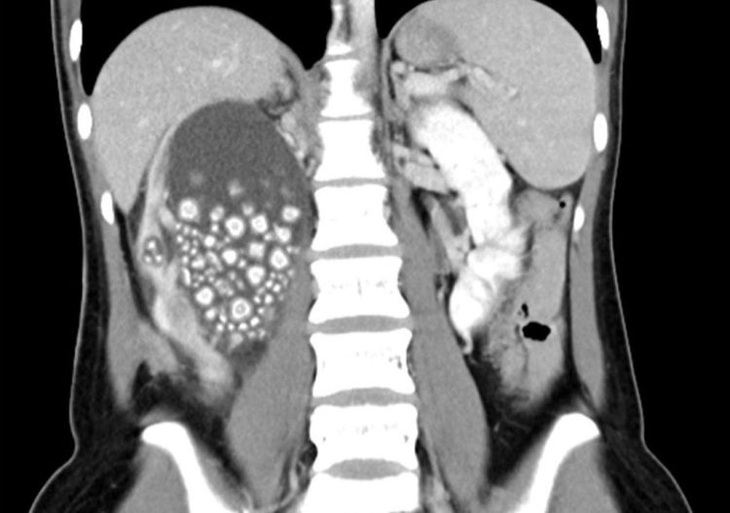

Thận phải của Xiao Mei có hàng trăm viên sỏi "chen chúc" nhau - Ảnh: Chi Mei Hospital

Trang Independent cho biết thêm khi chụp CT, kết quả cho thấy thận phải của Xiao Yu có hàng loạt viên sỏi có kích thước to nhỏ khác nhau, từ 5mm đến 2cm. Thậm chí, chúng trông giống như những... chiếc bánh bao hấp phiên bản mini.

Các bác sĩ đã phải mất 2 giờ để gắp thành công khoảng 300 viên sỏi từ thận của Xiao Yu ra ngoài, nhờ phương pháp mổ nội soi.